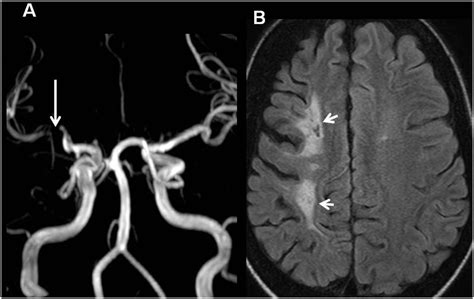

• Imaging tests: MRI or CT scans to look for evidence of brain damage.

• Carotid ultrasound: To check for narrowing or blockages in the carotid arteries.